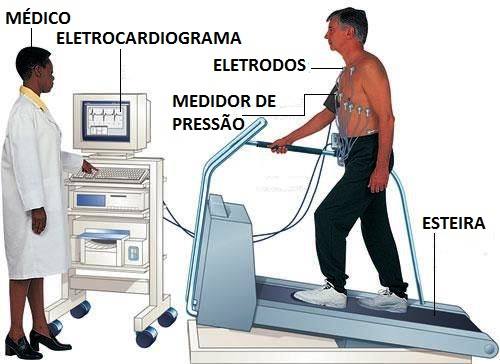

- Teste Ergométrico (Teste de Esforço)

O Teste de Esforço é mais conhecido como “Teste da Esteira” por ser realizado em uma esteira semelhante aquelas encontradas nas academias.

A principal função do teste é a de monitorar a resposta do coração diante do esforço físico.

Inicialmente são colocados eletrodos no corpo do paciente e em seguida ele deve começar a andar numa esteira.

Aos poucos a intensidade do exercício , controlada por um especialista, vai aumentando.

Entre o início e fim de cada ciclo, são registradas a pressão arterial, o ritmo e a frequência cardíaca.

O tempo de duração do teste de esforço é de cerca de oito minutos e ele pode ser interrompido caso o paciente demonstre exaustão.

Durante o teste o médico tem a possibilidade de avaliar a capacidade cardiovascular, identificar a isquemia e obter informações que auxiliarão na definição de limites seguros de intensidade de exercícios.

Se o teste na esteira não for recomendável ele pode ser feito em uma bicicleta ergométrica.